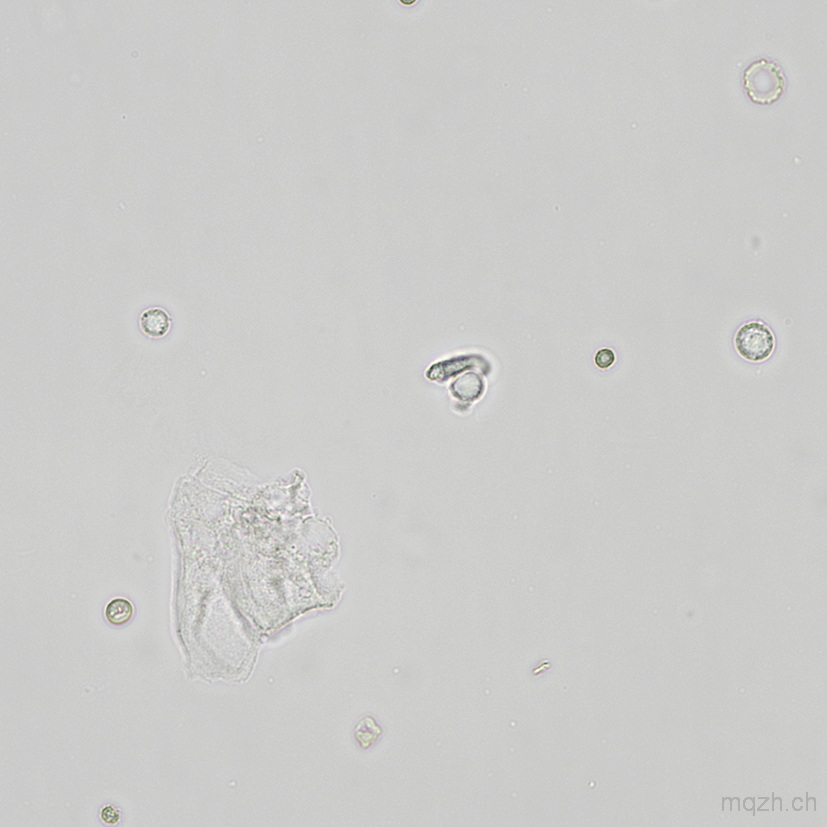

MQ 2025-4 Urinary Sediment U4